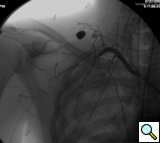

The patient is positioned supine with the ipsilateral upper extremity prepped out at a 90º angle and with both groins and chest prepped in as well. The right femoral artery is percutaneously engaged in a standard Seldinger technique with a standard short 5F sheath. We utilize an 0.035 inch hydrophilic angled Glidewire® (Terumo Medical Corporation, Somerset, NJ), which is brought up into the ascending aorta and followed with a JR4(C.R. Bard Inc. Murray Hill, NJ) catheter. The C-arm is positioned in a 25º LAO view to “open the arch” and the aortogram is commenced delineating the arch and arch vessel anatomy. Gentle traction and pullback on the catheter allows us to engage the target arch vessel, selectively advancing the Glidewire into the appropriate vessel. Next, once the wire is placed far distally the catheter is gently advanced into the appropriate vessel where selective angiograms are performed (Figure 1). Inability to traverse the transected subclavian artery may mandate a retrograde transbrachial approach.

![]() |

| Figure 2: Post deployment of angled glide wire and JR4 catheter past the transected subclavian artery revealing patent vessel distally. |